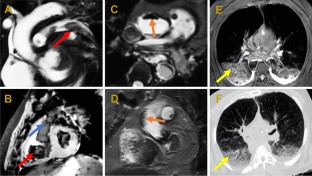

Conventional autopsy is the gold standard for identifying unexplained death but due to declines in referrals, there is an emerging role for post-mortem imaging. We evaluated whether post-mortem magnetic resonance (PMMR) and computed tomography (PMCT) are inferior to conventional autopsy. Deceased individuals ≥ 2 years old with unexplained death referred for coronial investigation between October 2014 to December 2016 underwent PMCT and PMMR prior to conventional autopsy. Images were reported separately and then compared to the autopsy findings by independent and blinded investigators. Outcomes included the accuracy of imaging modalities to identify an organ system cause of death and other significant abnormalities. Sixty-nine individuals underwent post-mortem scanning and autopsy (50 males; 73%) with a median age of 61 years (IQR 50–73) and median time from death to imaging of 2 days (IQR 2–3). With autopsy, 48 (70%) had an organ system cause of death and were included in assessing primary outcome while the remaining 21 (30%) were only included in assessing secondary outcome; 12 (17%) had a non-structural cause and 9 (13%) had no identifiable cause. PMMR and PMCT identified the cause of death in 58% (28/48) of cases; 50% (24/48) for PMMR and 35% (17/48) for PMCT. The sensitivity and specificity were 57% and 57% for PMMR and 38% and 73% for PMCT. Both PMMR and PMCT identified 61% (57/94) of other significant abnormalities. Post-mortem imaging is inferior to autopsy but when reported by experienced clinicians, PMMR provides important information for cardiac and neurological deaths while PMCT is beneficial for neurological, traumatic and gastrointestinal deaths.